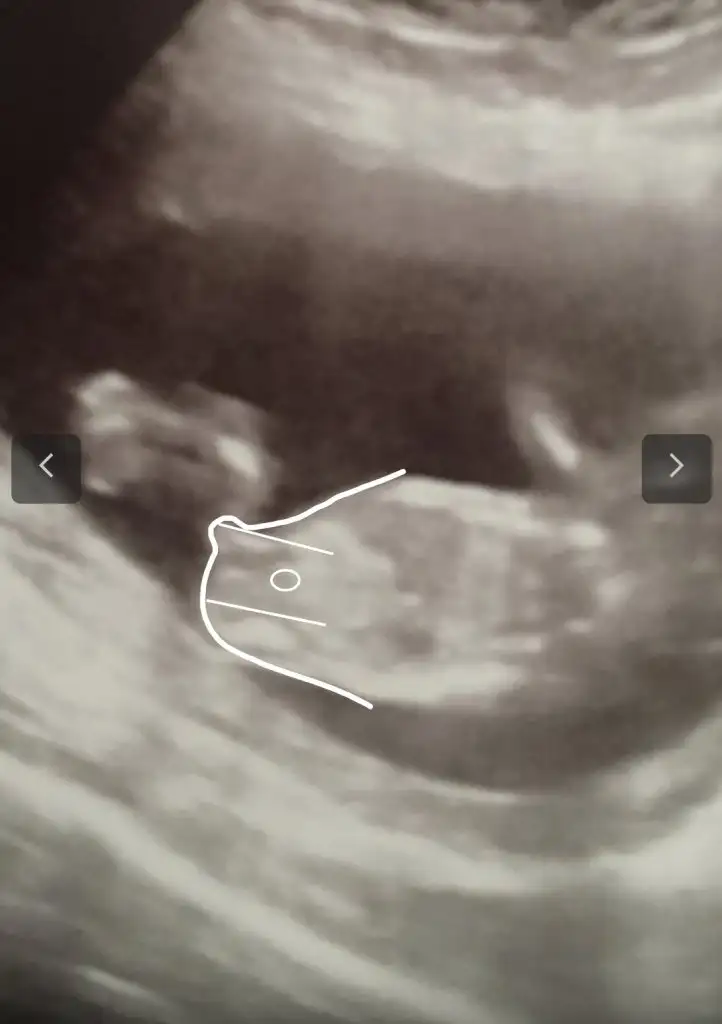

Merhaba. Rica etsem benim usmya tahmin yapar mısınız?

12+2 günlüktü burda. Karından detaylı ultrasondu.

Doktor benzetme yaptı ama kesin değil dedi.doktorla aynı olursa oyumu veririm❤️

Kız sanki başka USG varsa paylaşın